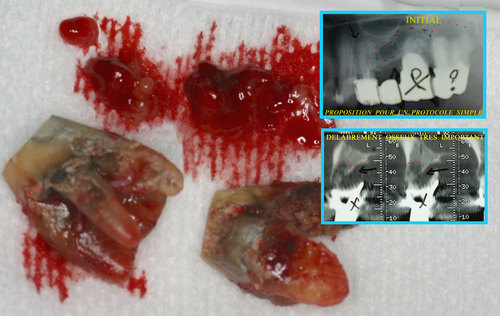

Les infections des dents provoquent des lésions osseuses avec disparition du volume osseux au fur et à mesure que l’infection se propage dans l’os des maxillaires. (fig. 29)

Fig. 29

Les infections dentaires provoquent des pertes osseuses importantes

Cela interdit souvent le port d’une prothèse correcte ou la mise en place d’implants en remplacement des dents absentes.